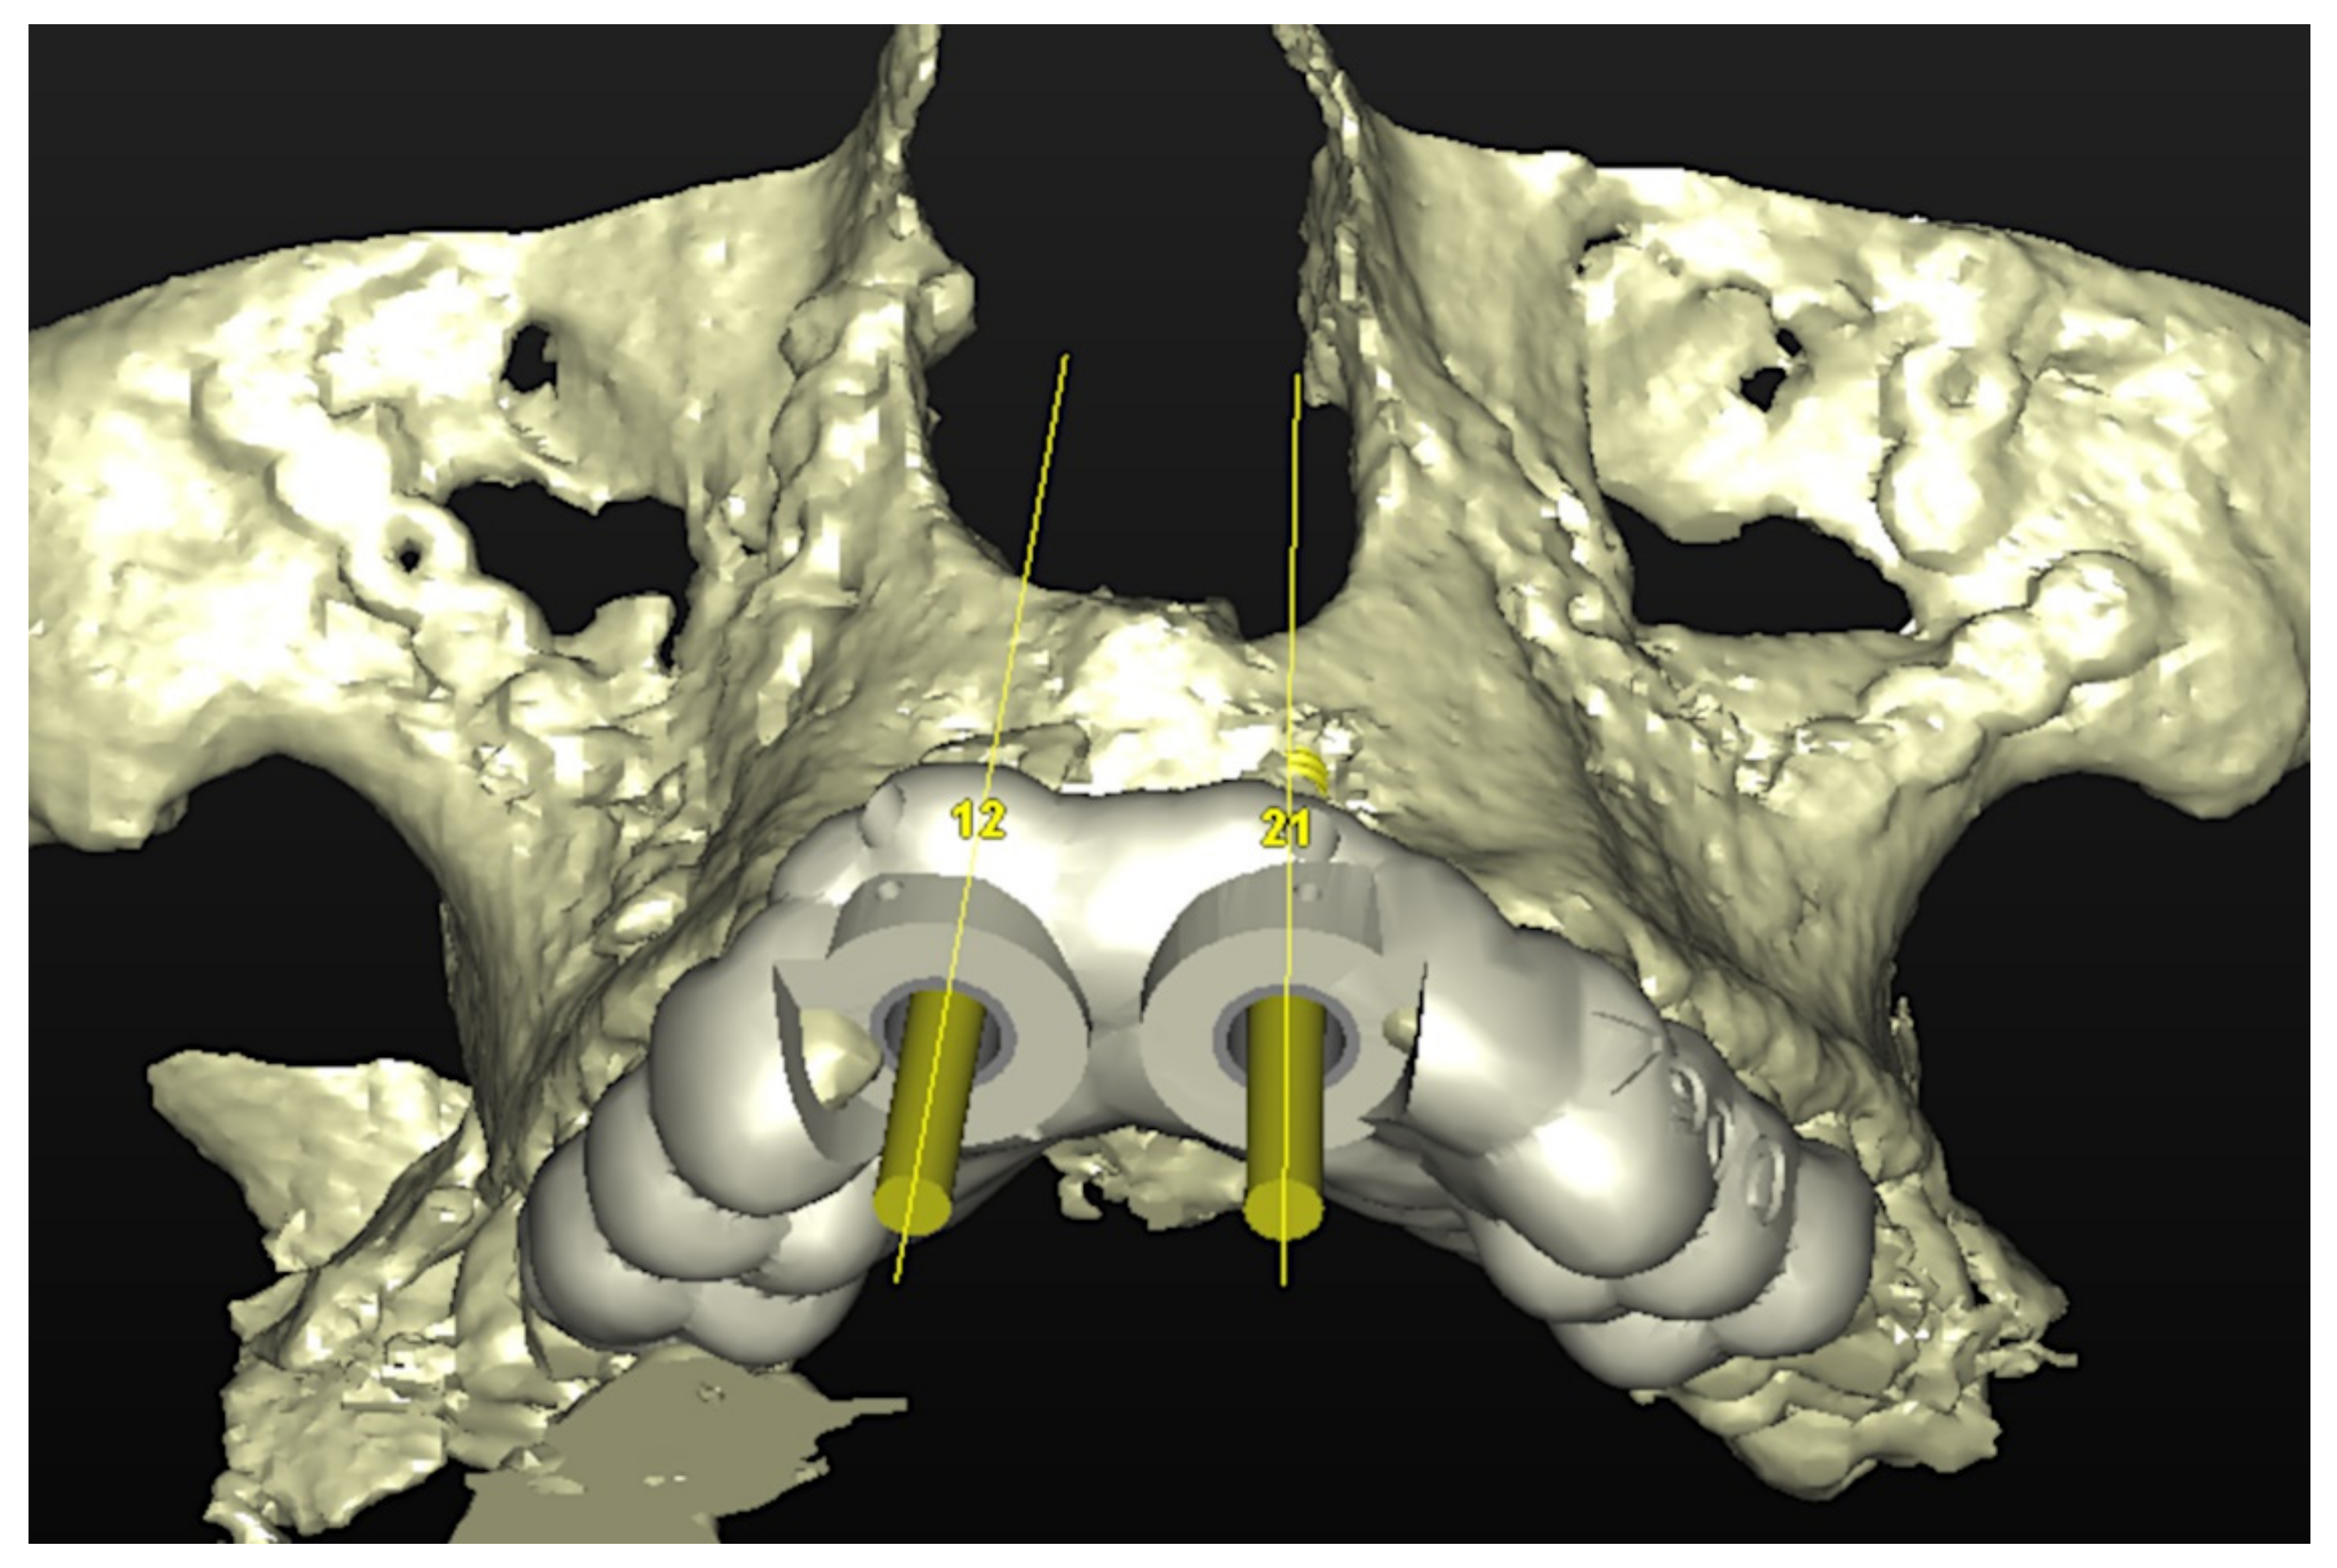

Figure 4.

Planning of the number, the diameter, and the axis of the implant with respect to the design of the final prosthesis.

In November 2017, two guided dental implants were placed at sites # 12 and # 21 (Figure 7, Figure 8, Figure 9, Figure 10 and Figure 11).